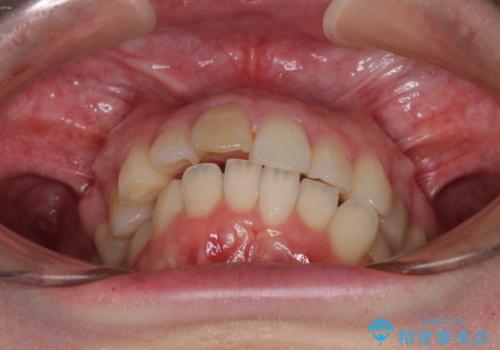

- 上顎前歯の突出感と、前歯のクロスバイトを気にして来院された患者様です。

前歯の叢生と口元の閉じにくさを気にして来院された患者様です。

奥歯の咬み合わせを見ると、上顎が下顎に対して相対的に前方にありました。